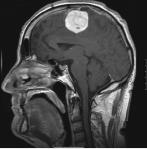

Tumoren

Behandlung von Kalottentumoren mit Kalottendefektdeckung